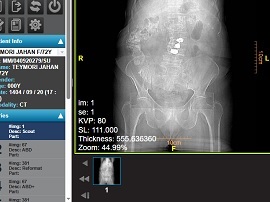

سی تی اسکن

سی تی اسکن روشی در تصویربرداری پزشکی است که با اشعه ایکس تصاویر قابل تفسیر تهیه می سازد و برای نواحی احشاء شکمی مانند روده که نیاز به شفاف بودن برای تشخیص دقیق است علاوه بر ماده تزریقی از ماده حاجب خوراکی نیز کمک گرفته می شود. همچنین سی تی اختصاصی روده به نام سی تی کونوسکوپی یا کولونوگرافی با سی تی ، به جهت بررسی پولیپ روده ، بیماریهای التهابی روده و سرطان روده بزرگ کاربرد دارد به گونه ای که هوا یا ماده کنتراست به روده بزرگ تزریق می شود.

چنانچه ذکر شد فیلم رادیولوژی روده همان فیلم سیاه و سفید و خاکستری است که پس از اتمام تصویربرداری های فوق تصاویر منتخب بر روی آن به چاپ می رسد. فیلم رادیولوژی روده به پزشک کمک می کند تا مشکلات روده کوچک و روده بزرگ بیمار شامل تنگی یا انسداد ، توده های کوچک یا بزرگ ، بیماری کرون و ... را بخوبی بررسی کند.